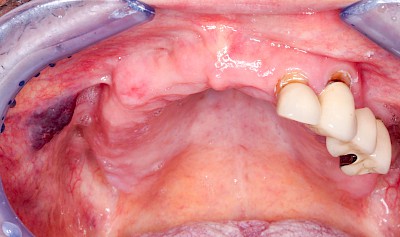

Wundheilungsstörungen

Nach operativen Eingriffen im Bereich der Mundhöhle (Zahn ziehen "Extraktion", Schleimhautprobenentnahmen "Biopsien" oder Tumoroperationen) kann es zu Wundheilungsstörungen mit Schwellungen, Rötungen und Nach-Blutungen, gestörter Sprache oder Kaufunktion kommen. Einzele Gesichtsbereiche können sich warm anfühlen und in seltenen Fällen kann es zu Fieber und reduziertem Allgemeinzustand kommen.

Wundheilungsstörungen24 Bilder

Mukositis bei Chemotherapie oder bei Strahlentherapie im Kopf-Hals-Bereich

Im Rahmen von Chemotherapie oder Strahlentherapie im Kopf-Hals-Bereich kann es zu schweren Entzündungen der Mundschleimhäute kommen (Mukositis).

Die chemo- bzw. strahleninduzierte Mukositis ist gekennzeichnet durch:

- Starke Schmerzen

- Großflächige Rötungen, z.T. mit Blutungen

- Großflächigen Blasen

- Schleimhautablösungen

Informationen zu Schleimhautentzündungen in Folge einer Chemo- bzw. Strahlentherapie im Kopf-Hals-Bereich finden Sie hier.

Beispiele23 Bilder